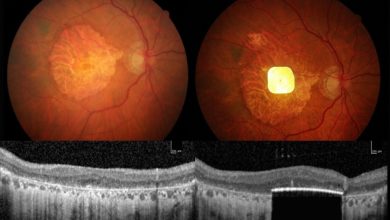

Implante ocular eletrônico e óculos AR restauram a visão de leitura em pessoas com perda de visão

Imagem do chip no olho de um paciente. Crédito: Corporação Científica Depois de serem tratadas com um implante ocular eletrônico…